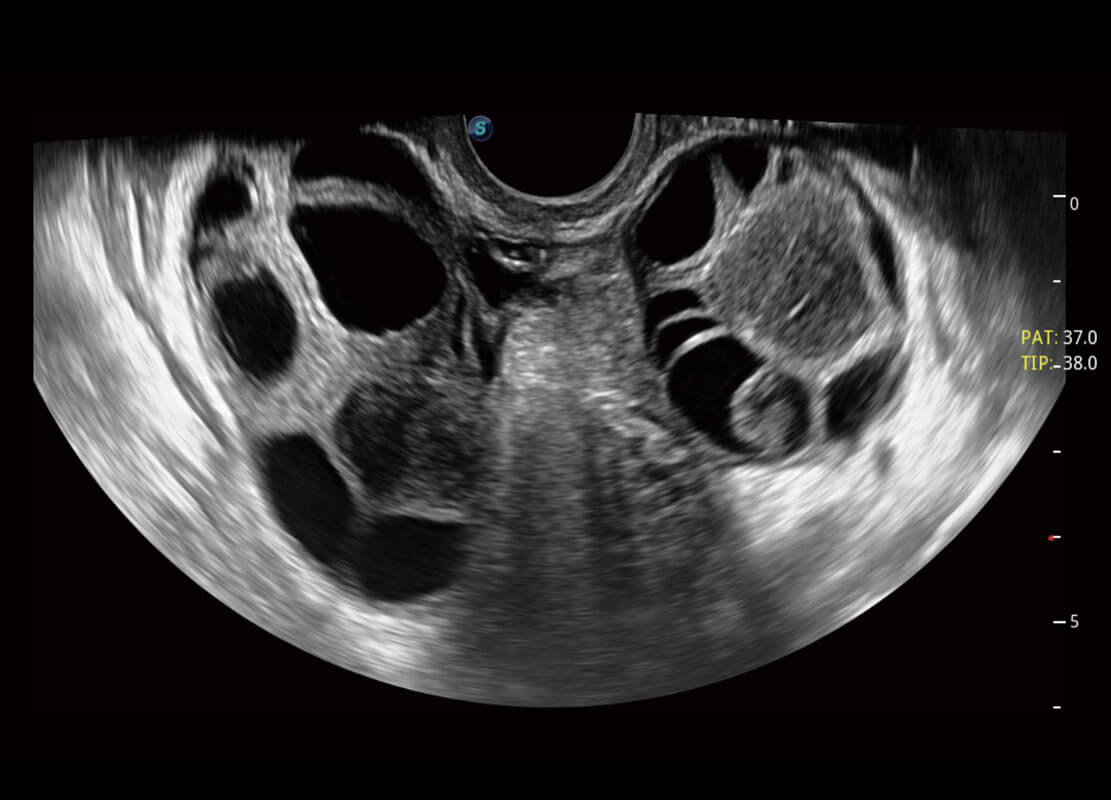

P60优异的图像质量搭载专科探头,在妇科基础疾病的诊断、卵泡生长的监测、输卵管通畅情况的判别等方面为您提供生殖应用方案。

腔内妇科-卵巢

P60为盆底超声检查提供应用方案,多种腔内及腹部容积探头提供从二维、三维到四维的优异图像品质,实时快速三维容积数据获取,专业的测量工具包等人性化设计,为超声医生诊断提供有力保障。

能够简化盆底检查的操作流程,可在二维模式及三维成像模式下实现一键自动提取出标准切面、自动识别当前切面、自动测量,提升盆底检查的高效性,同时也能让青年医生快捷的获得准确的检查结果。